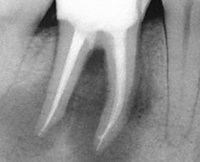

• Целевая рентгенография зубов. На рентгеновском снимке зуба уровень искусственного анастомоза в направлении файла может быть определен с помощью инструмента. При сложных рентгеновских перфорациях площадь искусственного отверстия соответствует истончению костной ткани с размытыми контурами.